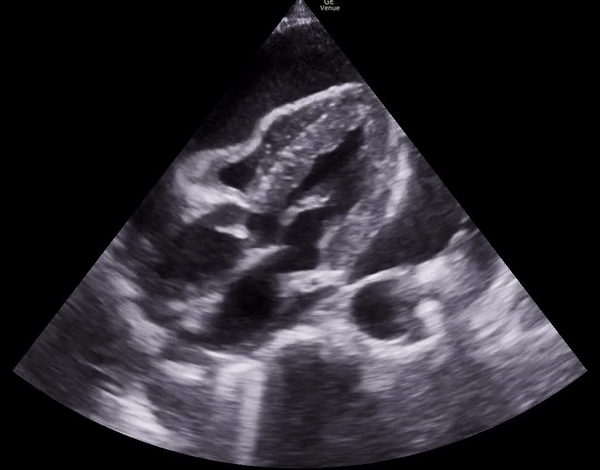

Parasternal short axis: right ventricular diastolic collapse.

Apical 4 chamber: diastolic RV collapse.